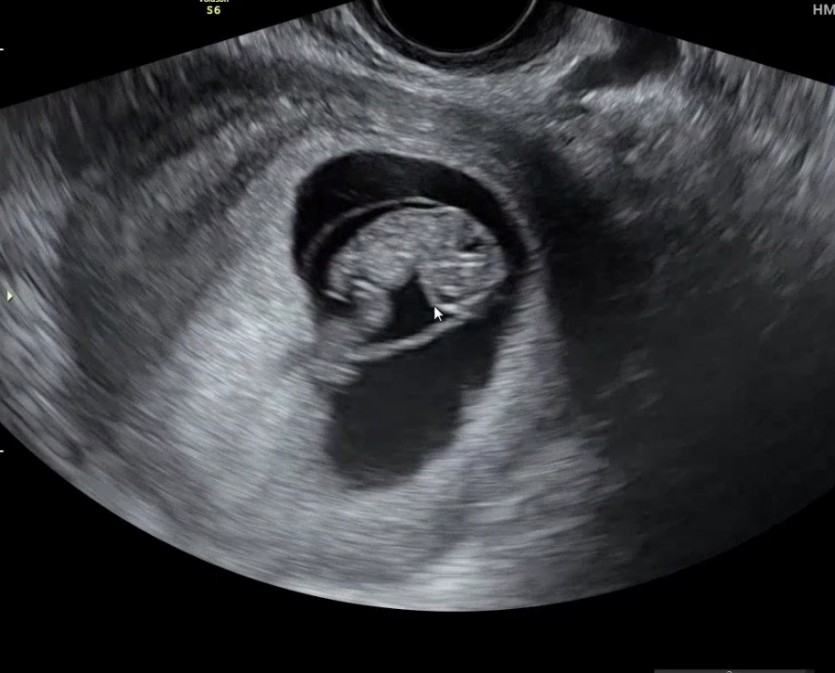

오늘 졸업초음파 기념으로 올려보아요

잘 따라와주신 결과가 위에 사진과 같이 예쁜아기인것같아요

초음파 사진이 너무 예쁘게 잘 나온것같아요 ㅎ,보기만해도 입가에 웃음이 번짐니다